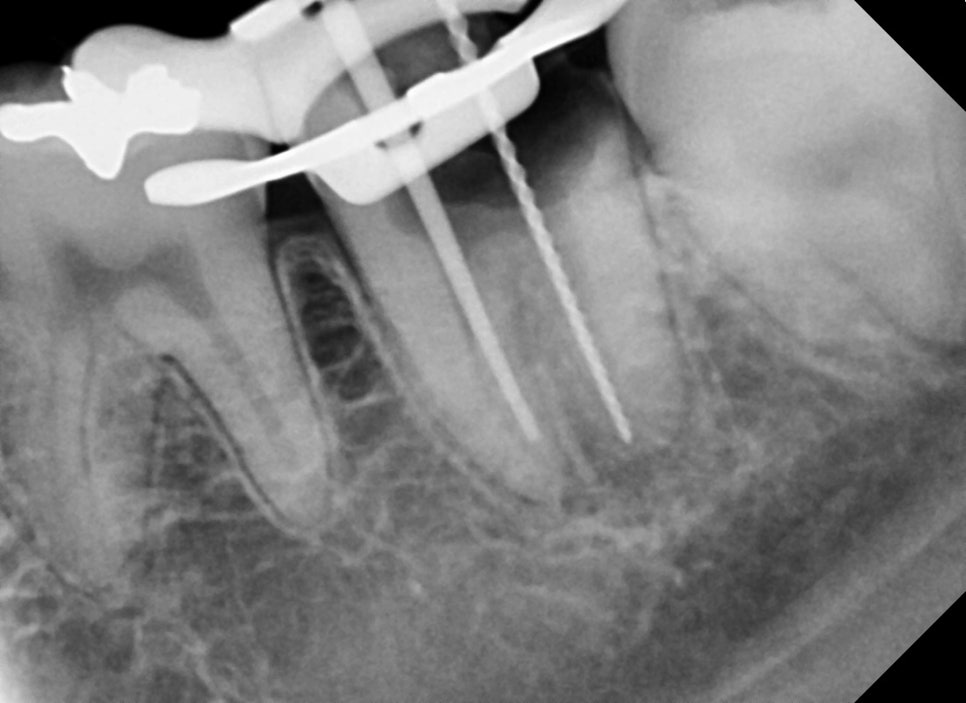

이번 케이스는 신경관의 구조는 엄청나게

복잡한 편은 아니었지만

신경관마다의 크기가 너무 컸기 때문에

신경치료를 하면서

신경관의 길이, 두께, 크기를 측정하기가 까다로웠고

그만큼 신경관 내부의 소독에 신경을 썼습니다.

측정기 구로도 애매한 여러 신경관들을 X-ray를 통해

좀 더 명확하게 확인하는 과정을 통했습니다.